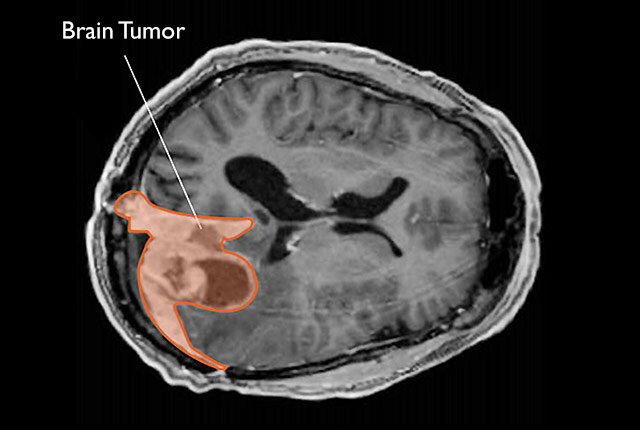

A 54-year-old British mother, Kerry Brown, mistook episodes of tingling, fatigue and hot flashes for menopause until an MRI revealed multiple brain tumors. Doctors initially found four tumors, but surgery uncovered a total of 10, with five removed. Brown subsequently faced seizures and partial blindness from optic nerve pressure, and two tumors have begun to grow again, necessitating radiation; she’s now sharing her story to raise awareness and funds for Brain Tumour Research.